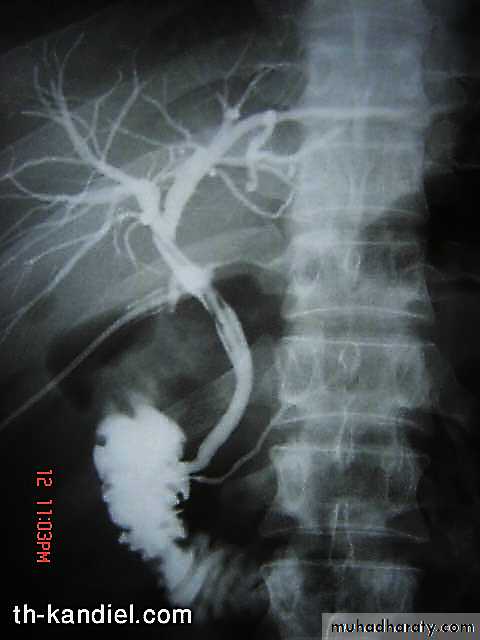

Cholangiogram: typical “beading” or “pruning” of extra- and/or intra-hepatic bile ducts (strictures).

MRCP (of choice)

ERCP (only if intervention is planned)